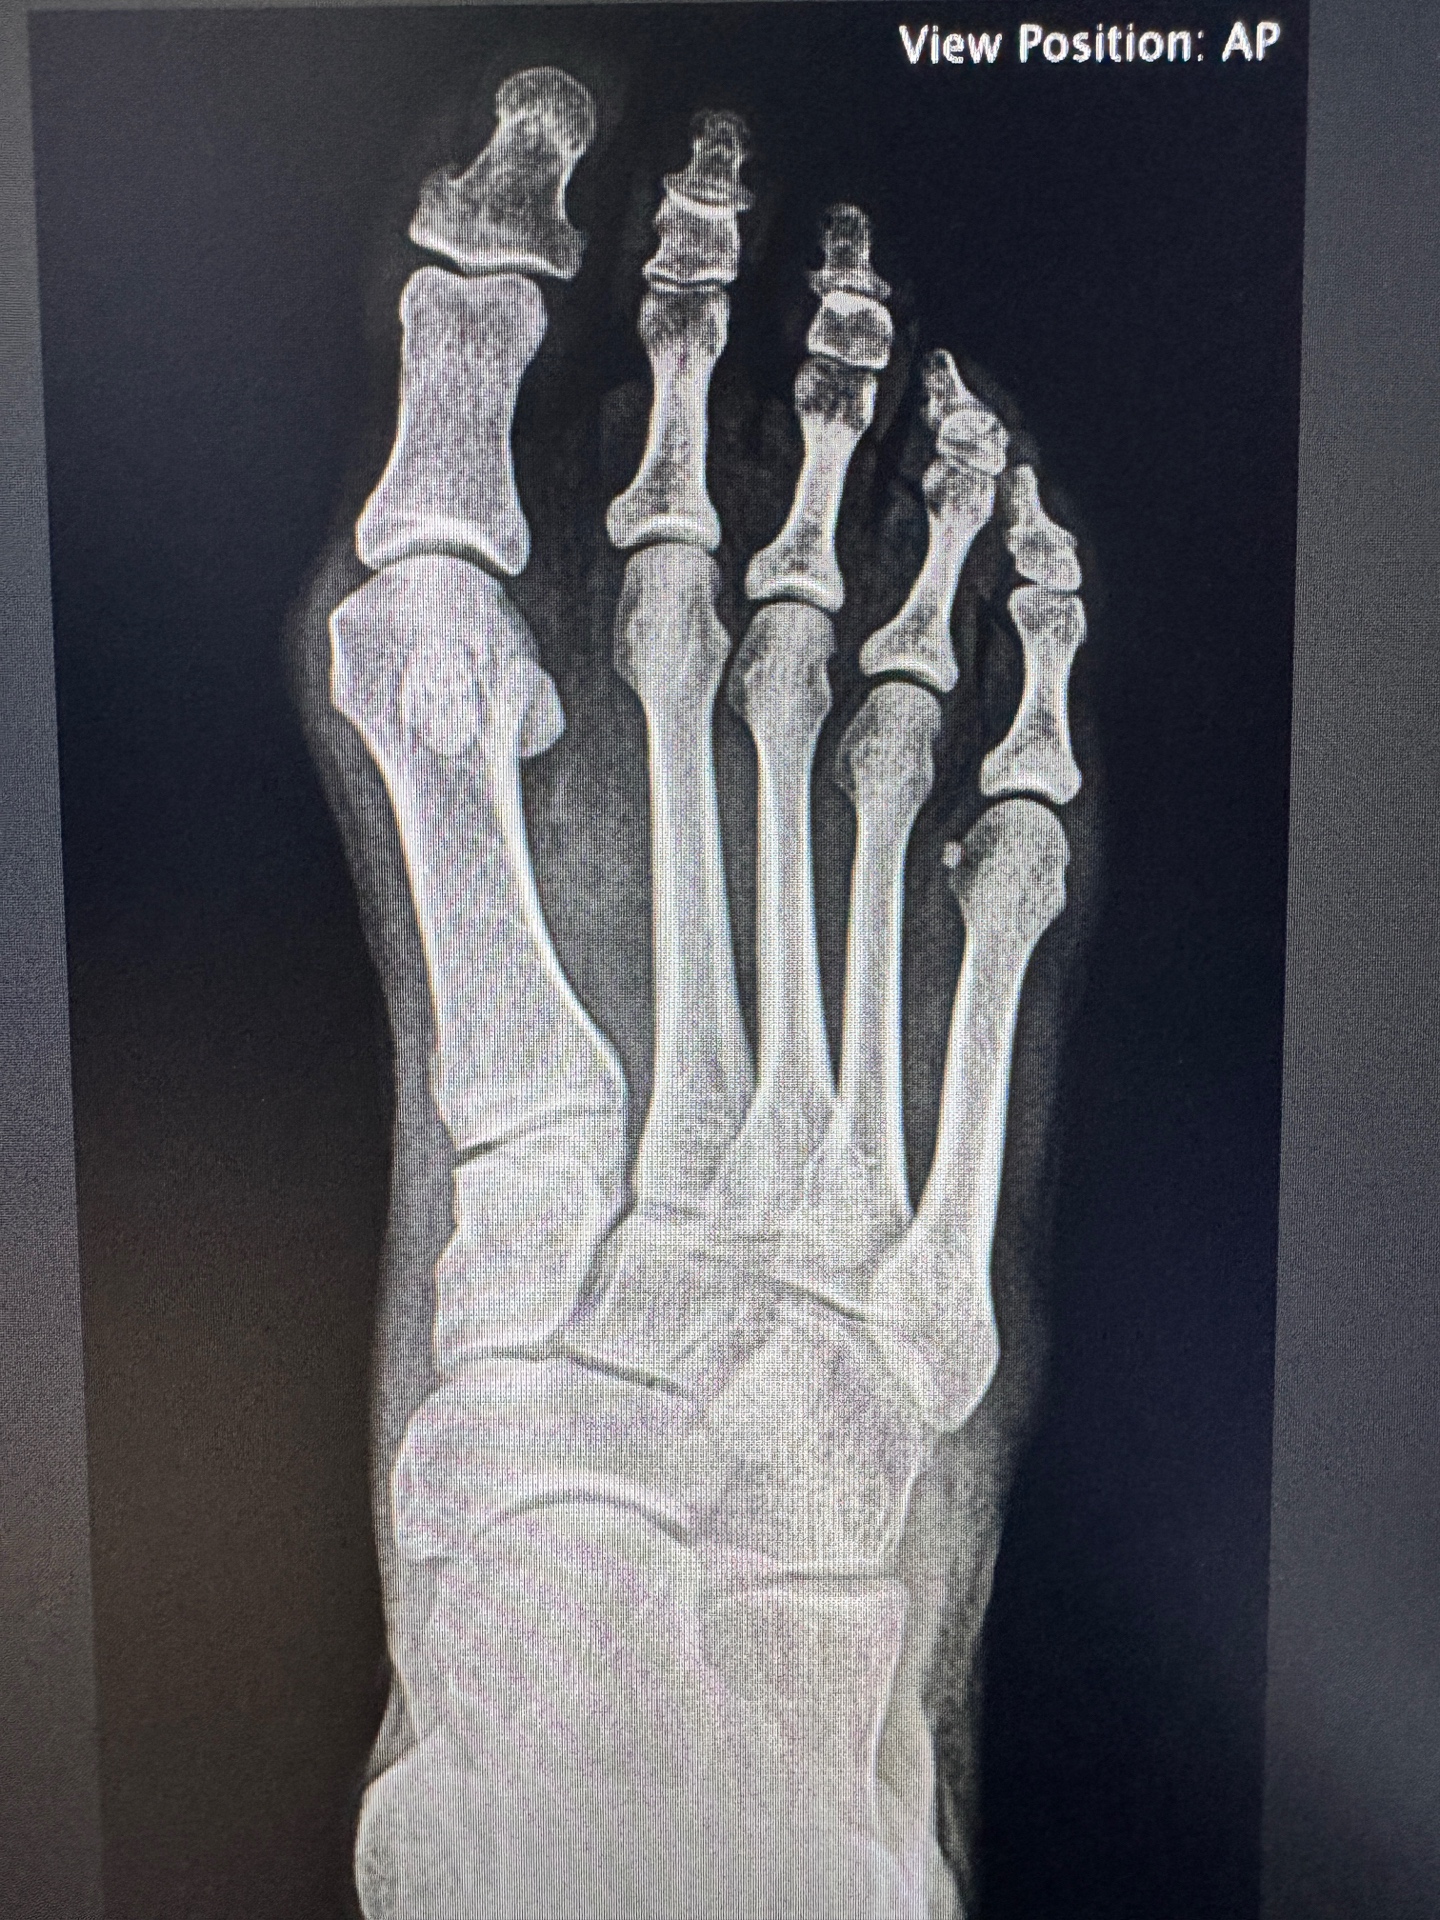

Patient X-Ray Results

Actual patient X-rays from Dr. Bregman's practice — showing deformity correction achieved through minimally invasive technique.

Bunion X-ray before minimally invasive surgeryBEFORE

Significant hallux valgus deformity with lateral deviation of the great toe